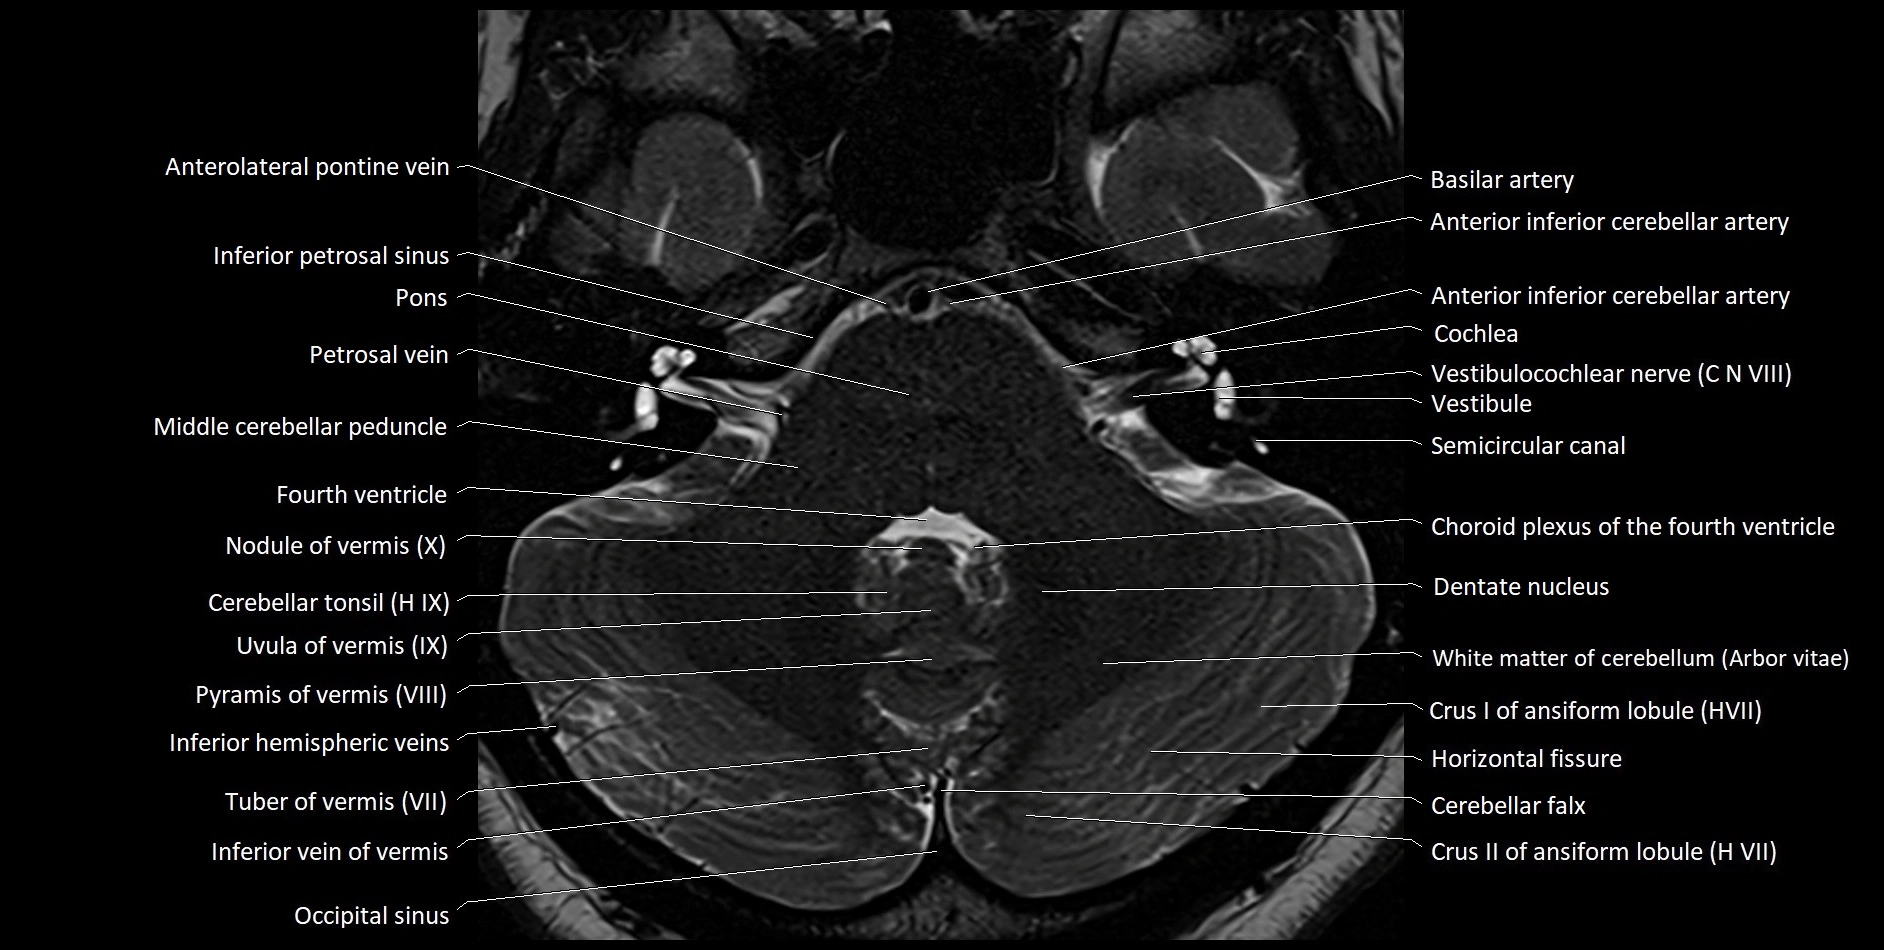

MRI images